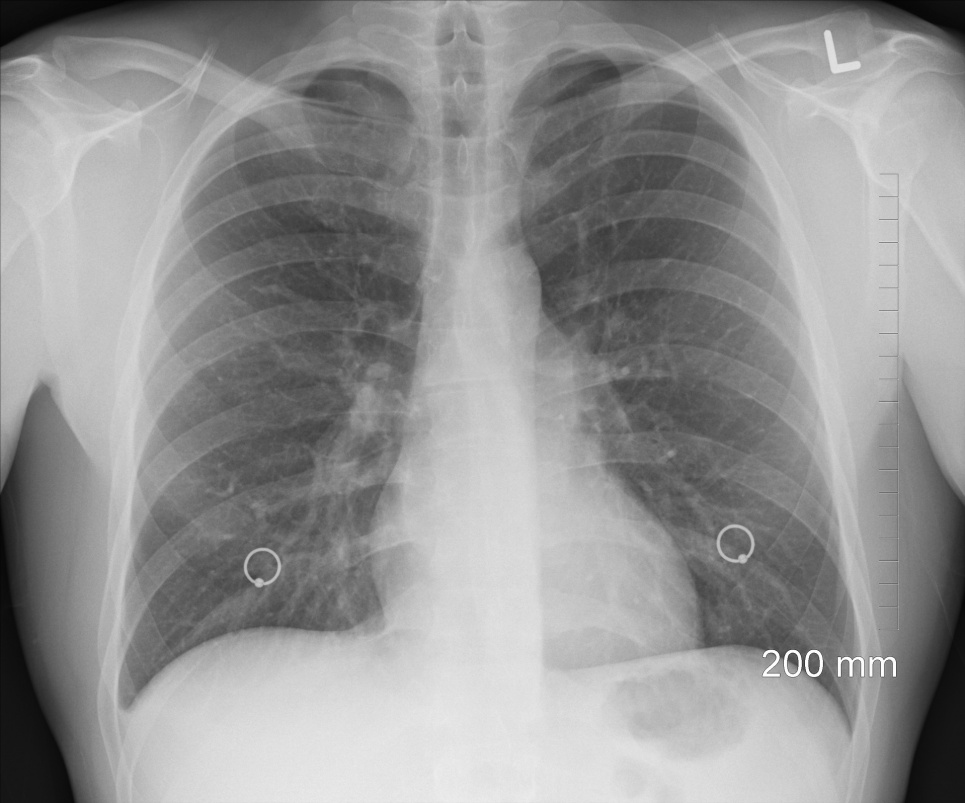

Медики використали технології віртуальної реальності, щоб продемонструвати вплив коронавірусу на легені людини. Відео демонструє легені 59-річного чоловіка у якого ще кількі днів тому не було ніяких симптомів коронавірусу.

"Ми бачимо, що легені швидко і прогресивно пошкоджувались, так що йому потрібні більш високі рівні підтримки від вентилятора, і це дійшло до того, що йому потрібна максимальна підтримка вентилятора", - сказав доктор Кіт Мортман, голова відділення торакальної хірургії лікарні Університету Джорджа Вашингтона.

"Існує дуже різкий контраст між зараженою вірусом легенею та більш здоровою сусідньою тканиною легенів. І між ними така різниця, що не треба бути професором медицини, щоб зрозуміти ці картинки. Це те, що широка громадськість може побачити і почати по-справжньому розуміти силу пошкодження легень. Пошкодження, які ми спостерігаємо, не обмежується жодною частиною легені. Це важке дифузне ураження обох легень", - заначив Мортман.